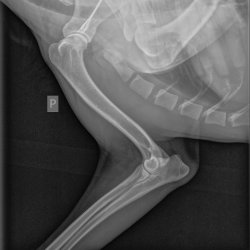

Příběhy Rocky s kulháním na pravou hrudní končetinu

Rocky s kulháním na pravou hrudní končetinu

Rocky je krasavec, se kterým se život nemazlil. Nejprve žil přivázaný u stromu, poté se čas změnil a strom se vystřídal řetěz v kotci. Žil ve vlastních výkalech, bez dostatku čerstvé vody a krmiva. Až po dlouhém nekonečném čase přišla záchrana, a to v podobě tet z Voříškova. Rocky k nim přišel na začátku tohoto roku celý pohublý, kulhající, se zažívacími potíži a s velkým strachem z cizích lidí.

Protože kulhání na pravou hrudní nožičku stále přetrvává, vzaly minulý týden Rockyho tety z Voříškova na vyšetření k panu doktoru.

RTG snímek Rocky